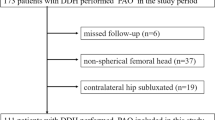

The study was a prospective case series study conducted at Aarhus University Hospital, Denmark. Patients were recruited and operated on between September 2013 and January 2014. Informed consent was obtained from all individual participants included in the study. Ethical approval was obtained from the Central Denmark Region Committee on Biomedical Research Ethics (Journal Number: M-20100274), and the study was registered at Clinical Trials.gov (NCT02015247). In the inclusion period, all patients (\(n=65\)) with hip dysplasia scheduled for PAO were identified and considered for inclusion. Inclusion criteria were: radiological diagnosed dysplasia (center-edge angle \(< 25^{\circ }\)), osteoarthritis degree \(\le 1\) according to the criteria of Tönnis and Heinecke [20], and hip pain. Exclusion criteria were: Legg–Calvé–Perthes disease, neuromuscular diseases, previous major hip surgery, persons with cognitive problems, and age < 18. Due to the need for cleaning and sterilizing the navigation instruments between surgeries, only one patient could be included per day of operation. When multiple candidates were available, the final decision was left to the discretion of the senior author (KS) and the most technically challenging patient was selected. In particular, patients with a retroverted acetabulum were included to evaluate the reliability of the system with a range of cases typically seen in clinical practice.